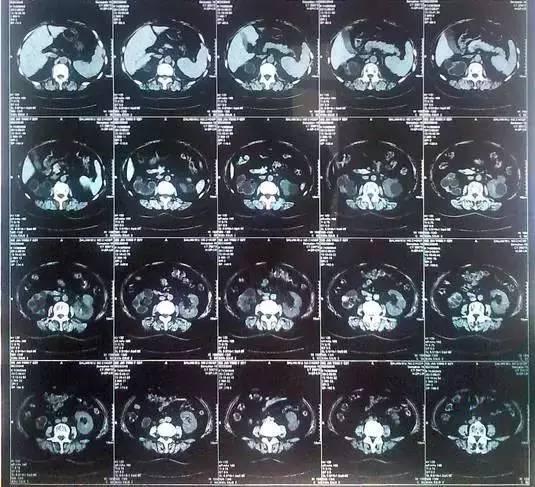

2.   55歲的老何是金華東陽市橫店鎮人,一名普通工人。因為頻繁腰疼去醫院檢查,結果CT顯示,他的左腎里竟然密密麻麻布滿了石頭,幾乎把整個腎都塞滿了,手術從左腎取出了420顆結石!

醫生看了CT的結果顯示,非常嚴肅的告訴他,他的左腎已經被結石占滿,必須馬上手術治療。這次手術讓主刀醫生觸目驚心,他們居然從老何的左腎取出了420顆結石。這是他們手術生涯上從來沒有遇到過的病例。